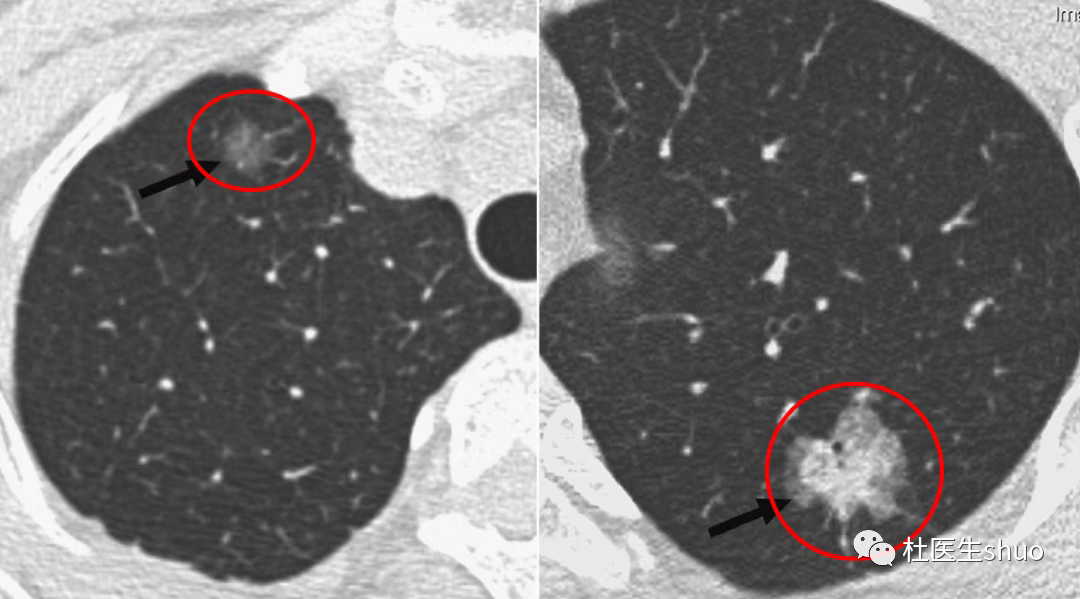

长期且持续存在、实性成分比例增加的肺部磨玻璃结节,这种结节就需要注意了。

如果持续复查多次胸部CT,提示结节增大或磨玻璃结节实性比例增加时,可考虑外科手术。

特别是影像学提示可能是微小浸润腺癌、浸润腺癌时,建议手术治疗。